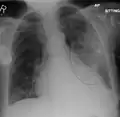

| A chest X-ray showing a very prominent wedge-shape bacterial pneumonia in the right lung | |

Normal AP CXR

AP CXR showing left lower lobe pneumonia associated with a small left sided pleural effusion -

AP CXR showing right lower lobe pneumonia -

AP CXR showing pneumonia of the lingula of the left lung -

Right upper lobe pneumonia as marked by the circle. -

Left upper lobe pneumonia with a small pleural effusion.

Right lower lobe pneumonia as seen on a lateral CXR